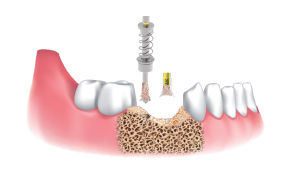

采集顺序 :

植入部位使用 Ø3.5/4.0

带硅保护帽的Harvesting Drill

使用点钻头采集骨片并标记植入部位。

选择Ø3.5/4.0钻,与塞子连接(Shield提前与Ø3.5&4.0塞子结合)。

一边注水,一边以300~500rpm的速度钻孔并采集骨片。

分离Shield和塞子,收集骨移植所需要的骨片。

根据制造商的钻孔方案使用最终钻(大于或等于Ø3.5/4.0)。

植入种植体

将采集的骨片植入缺损部位。